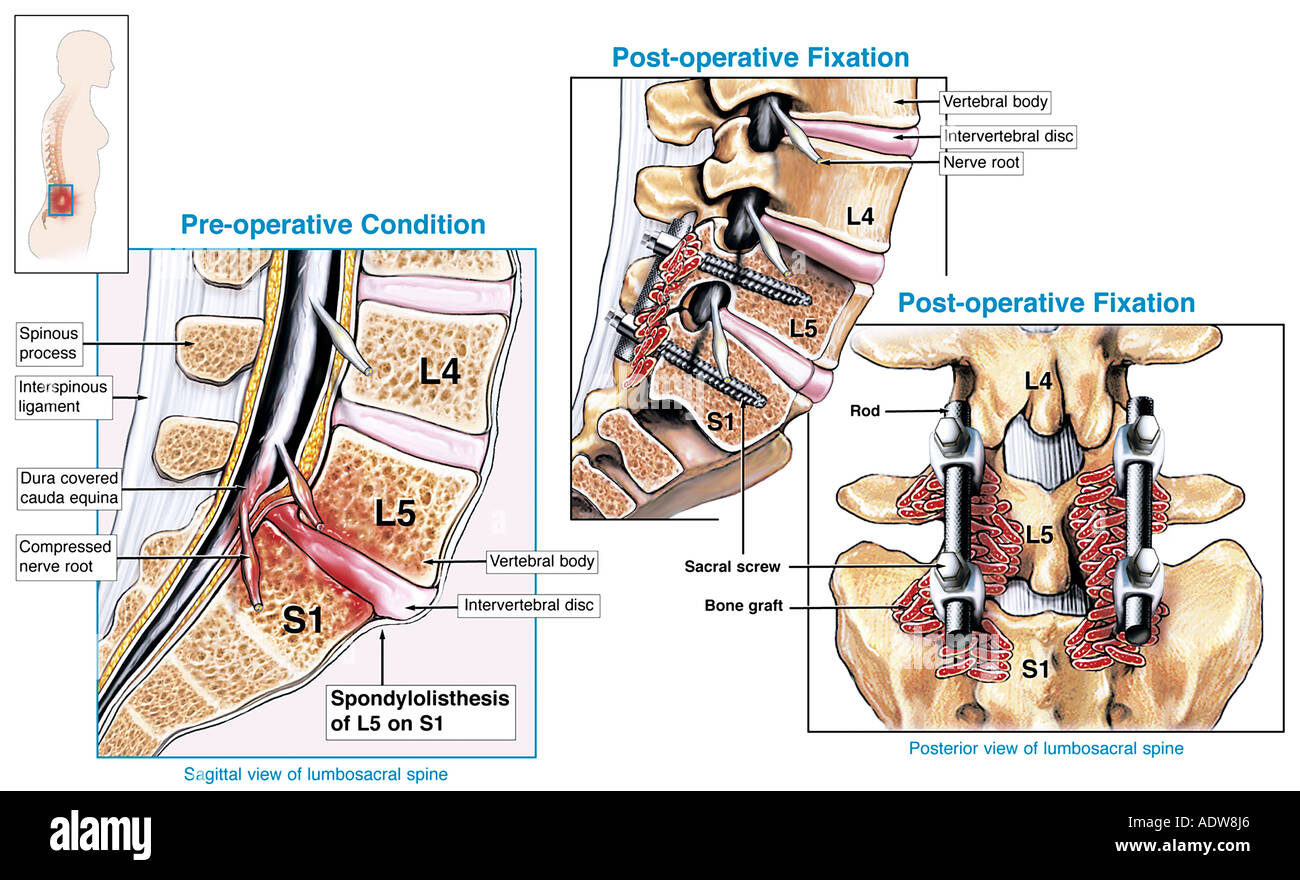

Spondylolyse et spondylolisthésis isthmique sont des aspects différents d’une affection dont la variabilité clinique est remarquable. Quantification du glissement. Clinique. Spondylolyse isthmique. Clinique. Imagerie. Formes cliniques. Indications thérapeutiques. Techniques chirurgicales.. La lyse se située plus souvent à l’étage L5/S1 mais peut parfois se retrouver à l’étage L4/L5. il est habituel que classer le glissement, occasionné par la lyse, en 4 stades de Meyerding. TRAITEMENT. Avant tout il est médical avec des antalgiques, de la rééducation associée au besoin à des infiltrations.

Benjiski Arthrodèse L4/L5/S1 les 10 et 18 octobre 2019 Page 3 Arthrodèse lombaire

Le spondylolisthésis implique habituellement les vertèbres L3-L4, L4-L5 ou le plus souvent L5-S1. Les types II (isthmique) et III (dégénératif) sont les plus fréquents.. Dans la majorité des cas, le spondylolisthésis concerne les vertèbres les plus basses, surtout au niveau de la jonction entre la colonne lombaire et le début de la colonne sacrée. La localisation entre la 4e et la 5e vertèbre lombaire est la plus commune : on parle de spondylolisthésis L4-L5.